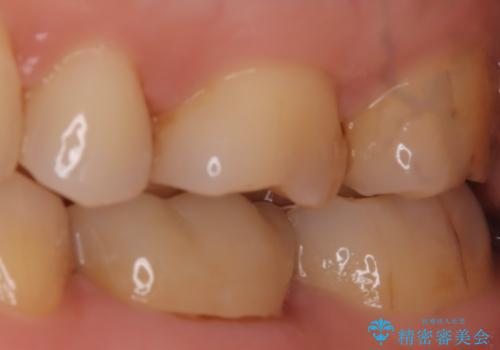

【セラミックインレー】適合の良いセラミックインレーを入れたい。

- 毎回フロスが引っかかることを気にされており、改善のため適合の良いセラミックインレーで修復しました。

以前に他院で詰め物をいれた時は、フロスが毎回ちぎれて大変だったそうですが改善して喜んでおられました。

当院のセラミックインレーは必ずラバーダムを使用して接着しています。